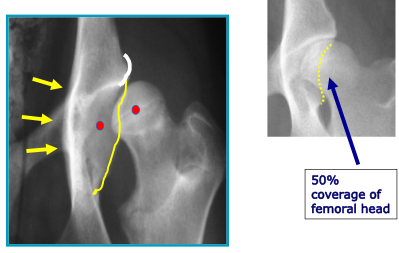

Want to look at dorsal acetabular rim: yellow squiggly line

The red dot on the femoral head should sit where the left red dot is in a non luxated hip.

Dorsal lateral acetabular ridge: White curve line looking at wear and tear on it

New bone: Yellow arrows. New bone seen in dorsal, ventral aspects of acetabulam and around the femoral head. A good indication joint is unhappy and under a degree of strain.

50% coverage of the femoral head is correct as seen in image